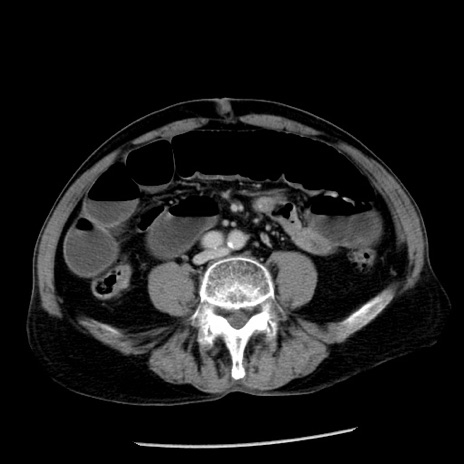

症例26(横断像)

【症例】80歳代男性

【主訴】嘔吐

【現病歴】昨晩2回嘔吐あり、今朝になっても嘔吐あり。来院。

【既往歴】胃潰瘍

【身体所見】意識清明、BT 37.6℃、BP 166/95mmHg、HR 100bpm、SpO2 97%、腹部:平坦・軟、腸蠕動音聴取良好、圧痛なし。

【データ】WBC 21900、CRP 1.46